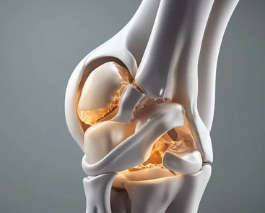

**퇴행성 관절염(Osteoarthritis)**은 나이가 들면서 관절의 연골이 닳아 없어지고, 관절을 이루는 뼈와 인대에 변화가 생겨 통증과 운동 제한이 나타나는 질환입니다. 흔히 ‘나이 들어 생기는 관절병’이라고도 불리며, 무릎, 손가락, 고관절, 척추 등 하중을 받는 관절에 주로 발생합니다. 이번 글에서는 퇴행성 관절염의 대표적인 증상, 초기·중기·말기별 변화, 감별 질환, 진단 및 관리법까지 자세히 정리합니다.

2. 증상 진행 단계별 특징

구분 증상 특징

| 초기 |

- 관절 사용 후 불편함

- 일시적인 통증

- 뻣뻣하지만 회복 빠름 | | 중기 |

- 움직일 때마다 통증 발생

- 계단, 앉았다 일어날 때 힘듦

- 관절 사이 간격 좁아짐 | | 말기 |

- 휴식 시에도 통증

- 관절 변형, 다리 휘어짐

- 걷기 불편, 보행 보조기 필요 가능 |

📌 말기로 갈수록 연골 소실과 뼈 마찰로 인해 생활 기능 저하와 만성 통증이 지속됩니다.